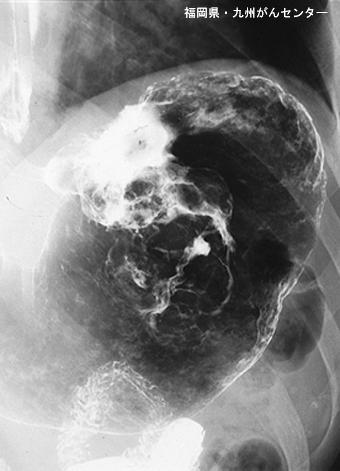

A case of Meckel diverticulum found during an operation for the gastric cancer.

Fukuoka Pref., National Hospital Organization Kyushu Cancer Center

Malignant epithelial tumor/Adenocarcinoma

Stomach/Body

X-ray

Type 5 Unclassfied type/

40 -

subserosa (subadventitia)